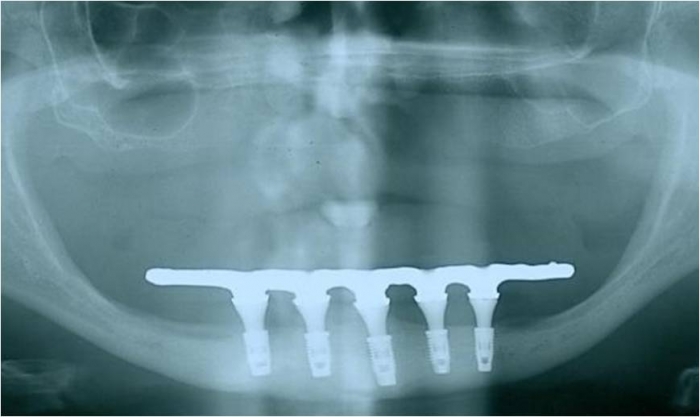

Raio X final com prótese fixa em resina instalada, sobre implantes Cone Morse

Raio X dos implantes Cone Morse